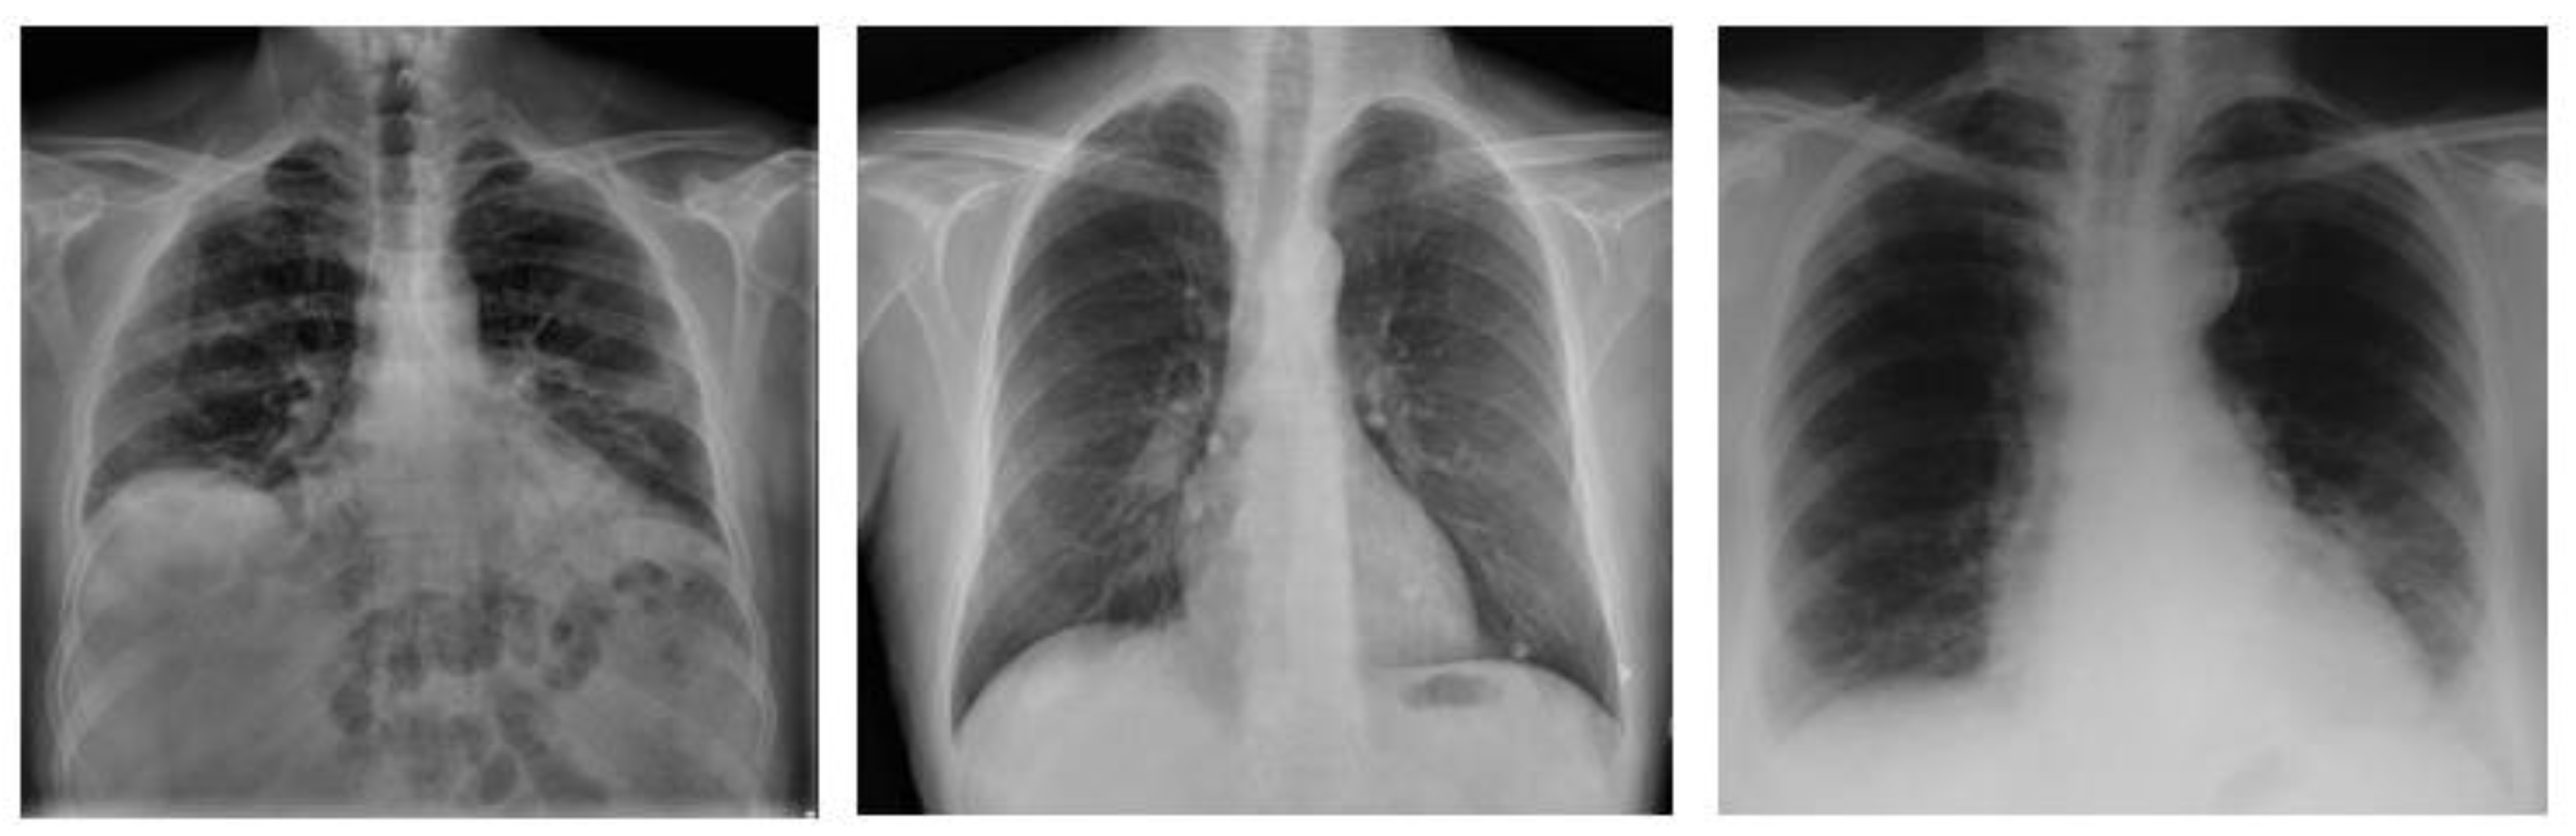

This research study used an open-source dataset of X-ray and CT scan images [17]. This dataset contains COVID-19 patient data, pneumonia patient data (caused by other diseases like MERS, SARS, and ARDS), and normal function data. These data were obtained by clinical experiments and from various hospitals [18]. Figure 2 illustrates the sample images from the dataset.

Figure 2. The sample images of the CT-scans and X-rays.